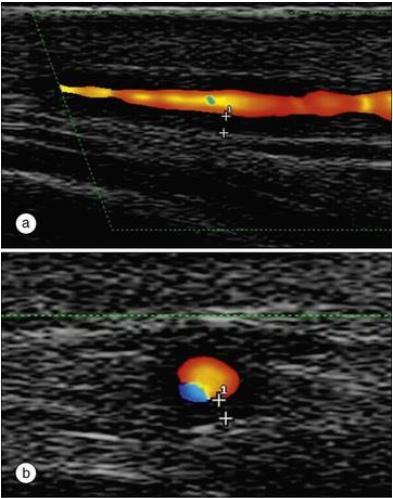

GCA病颞动脉超声:a图为纵切面;b图为横切面。双十字指示晕轮征

PMR病人的超声检查:肩峰下囊炎症和肱二头肌肌腱沟炎症